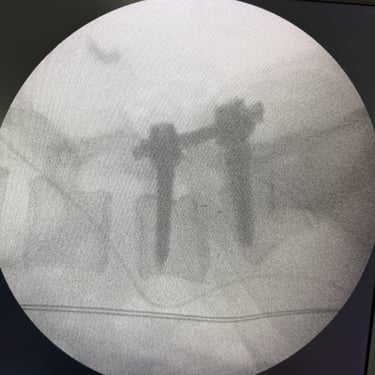

Listesis Lumbar L5–S1 por Fractura Ístmica: Estabilización con FTP y TLIF

La listesis lumbar L5–S1 por fractura ístmica se produce por un defecto en la pars interarticularis que genera inestabilidad vertebral, dolor lumbar crónico y compromiso radicular. Cuando el tratamiento conservador no es efectivo, la artrodesis lumbar con fijación transpedicular (FTP) asociada a la fusión intersomática transforaminal (TLIF) es una alternativa quirúrgica eficaz. Este procedimiento permite descomprimir las raíces nerviosas, restaurar la alineación vertebral y lograr una fijación sólida del segmento afectado. La combinación de estabilización y fusión reduce el dolor, mejora la función y favorece una recuperación segura y progresiva.